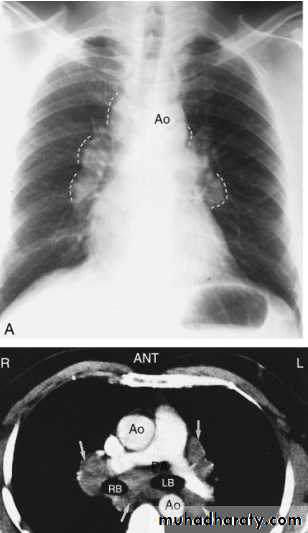

Sarcoid.

Marked lymphadenopathy (dotted lines) is seen in the region of both hila in the right paratracheal region (A).

The transverse contrast-enhanced computed tomography scan of the upper chest (B) clearly shows the ascending and descending aorta (Ao) as well as the pulmonary artery (PA) and superior vena cava. The right and left main-stem bronchus area also is seen. Arrows, the extensive lymphadenopathy.